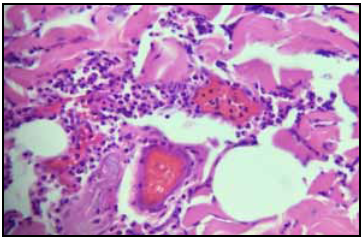

Dadas las características clínicas, su grupo etario y los resultados obtenidos en los paraclínicos, se solicitó valoración por oftalmología quienes sugerían neuropatía de ojo izquierdo, y se descartó polimiositis como causalidad, al no cumplir los criterios de Bohan y Peter (no presentaba lesiones cutáneas, mejoría clínica al administrar esteroides, enzimas musculares normales y ausencia de un patrón miopático en EMG), sugiriendo una neuropatía de pequeñas fibras, por lo que se inició manejo adicional con pregabalina y se realizó biopsia vascular y muscular (Figuras 1y2), con la cual se confirmó el diagnóstico de poliarteritis nodosa (PAN) al encontrarse un infiltrado inflamatorio mixto de predominio polimorfonuclear, linfocitos e histiocitos, y cumplía cinco de los 10 criterios de la ACR para PAN. Ante estos resultados se decidió iniciar manejo con ciclofosfamida (seis ciclos de 1 gr diluidos en 250 cc de SSN), prednisona oral 1 mg/Kg/día, azatriopina oral (50 mg c/12 h), ácido fólico (1 mg/día), con lo que se observó una evolución favorable y se lograron objetivos con el tratamiento instaurado, se dio salida de la institución con orden para volver mensualmente a sus ciclos de ciclofosfamida.

Figura 1 Biopsia vascular . Arterias de mediano calibre epimisiales, las cuales muestran inflamación perivascular con predominio linfoide, severo, cariorexis, asociados a hemosiderofagos y necrosis fibrinoide segmentaria de la pared.

Al realizar la biopsia se prefiere el abordaje menos agresivo (biopsia de piel o músculo), puesto que al tomar la muestra de órganos como el riñón o hígado se corre el riesgo de hemorragia 10. Generalmente se hallan infiltrados de linfocitos, macrófagos, neutrófilos, un número variable de eosinófilos, y en casos de lesiones activas se observa necrosis fibrinoide. En estados más avanzados, la formación de nuevos vasos se vuelve aparente. En lesiones avanzadas, la remodelación vascular conlleva al desarrollo de hiperplasia de la túnica íntima y cambios fibróticos difusos en la pared del vaso. La lesión severa de la pared puede resultar en la formación de microaneurismas y la trombosis puede contribuir también a la oclusión vascular 11-13.